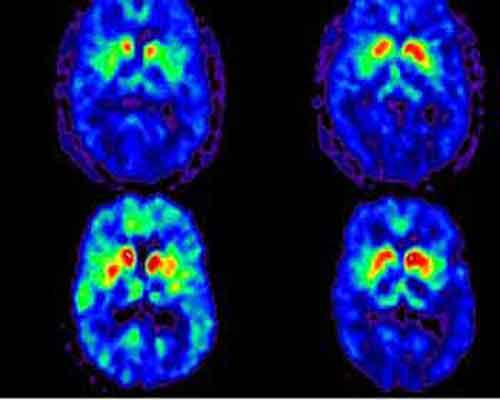

Il morbo di Parkinson è la seconda malattia neurodegenerativa, dopo il morbo di Alzheimer. Gli esperti dicono che circa 20.000 austriaci stanno lottando con questa malattia; circa il 10% delle persone è geneticamente predisposto. I sintomi tipici comprendono l’ipocinesia (movimento corporeo ridotto) e un caratteristico tremore. Capita più frequentemente negli uomini che nelle donne e diventa più comune con l’avanzare dell’età.